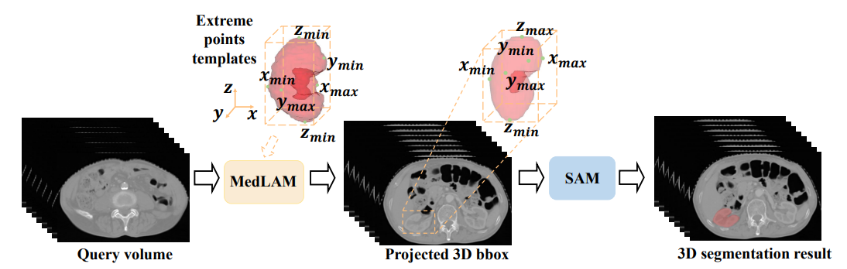

MedLAM

MedLAM:提出了一个使用 SAM 的医学数据集注释过程,并引入了一个少量定位框架。MedLAM 显著减少了注释负担,自动识别整个待注释数据集的目标解剖区域。